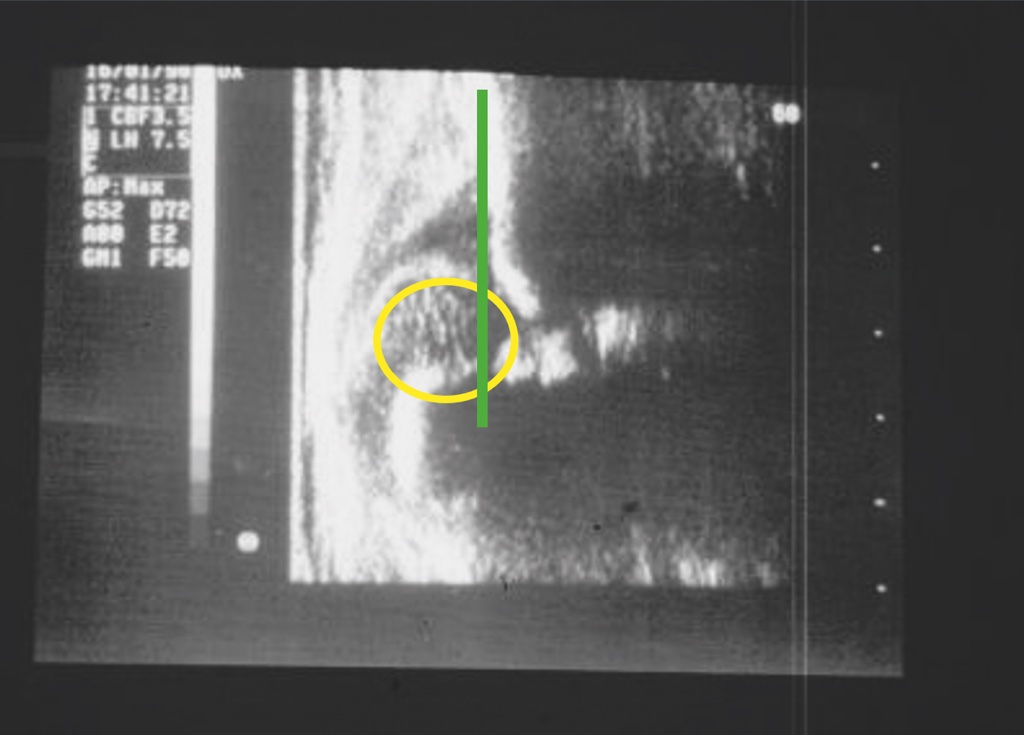

Oltre ai test clinici descritti che permettono un precoce sospetto diagnostico della displasia, viene comunemente utilizzato l’esame ecografico che ormai rappresenta un test estremamente affidabile; tale test, sebbene non ancora obbligatorio, viene praticato come screening diagnostico dalla quasi totalità dei neonati intorno alla ottava settimana di vita. Lo screening ha lo scopo di evidenziare casi di displasia non sospettati con l’esame clinico alla nascita che può risultare negativo anche se correttamente praticato. Nei casi in cui è presente una familiarità della patologia o i test di Ortolani/Barlow risultino positivi alla nascita, l’esame ecografico deve essere praticato per confermare il sospetto diagnostico nei primi giorni di vita. La diagnostica precoce della displasia evolutiva dell’anca permette di trattare conservativamente la patologia nel corso dei primi mesi di vita o comunque prima dell’inizio della deambulazione scongiurando l’evoluzione della patologia (Figg. 2-4).

L’esame ecografico è stato introdotto negli anni 80 da Graf che ha proposto una classificazione in quattro tipi per valutare condizioni di immaturità dell’anca (Tipo II) e condizioni più gravi come la sublussazione (Tipo III) e la lussazione franca (Tipo IV) 5. Il metodo è basato sulla valutazione dell’entità di due angoli: l’angolo α formato dalla linea di base che è rappresentata dalla continuazione verso il basso del profilo laterale dell’ala iliaca e la linea del tetto osseo mentre l’angolo β è formato sempre dalla linea di base e la linea del tetto cartilagineo. La radiografia dell’anca può essere attualmente utilizzata con lo scopo di confermare la diagnosi dopo i 4-6 mesi di vita. Nei casi di displasia è presente la caratteristica triade di Putti caratterizzata dalla sfuggenza del tetto acetabolare, dal ritardo di comparsa o dall’ipoplasia del nucleo di ossificazione della testa femorale che rappresentano segni di ritardo dell’ossificazione acetabolare e dall’allontanamento/risalita dell’epifisi prossimale del femore che viene valutata attraverso interruzione dell’ogiva o arco di Shenton. Tale ogiva è formata dal margine mediale della metafisi femorale che, in condizioni di normalità, si continua con il margine inferiore della branca ileo-pubica (Fig. 5).

Il tutore deve essere mantenuto sia nelle ore diurne che notturne per alcuni mesi fino alla guarigione della malattia che è rappresentata dal completo ripristino dell’ossificazione dell’acetabolo e dei rapporti articolari. L’avvenuta guarigione viene generalmente valutata con un esame ecografico, riservando l’indagine radiografica ai casi dubbi. La rimozione del tutore deve essere sempre graduale e pertanto, in una prima fase viene rimosso soltanto nelle ore diurne, continuando a mantenerlo di notte per un periodo di tempo ulteriore di uno/due mesi.